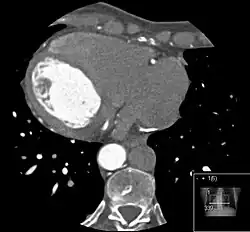

Die Azygoskontinuität der Vena cava inferior gehört zu den angeborenen Fehlanlagen des venösen Abstroms aus der unteren Körperhälfte. Die Vena cava inferior ist nicht durchgängig vorhanden, sondern es fehlt das Segment zwischen der Leber und den Nieren. Die Lebervenen drainieren wie bei der normalen Anatomie über ein kurzes hepatisches Segment nahezu direkt in den rechten Vorhof. Die Nierenvenen münden jedoch mit dem infrarenalen Segment der Vena cava inferior in die Vena azygos, die aufgrund des vermehrten Blutflusses deutlich weiter als normal ist. Diese mündet dann nach normalem Verlauf in die Vena cava superior. Es gibt eine Reihe von Variationen mit jeweils unterschiedlich ausgebildeten Gefäßabschnitten.[1]